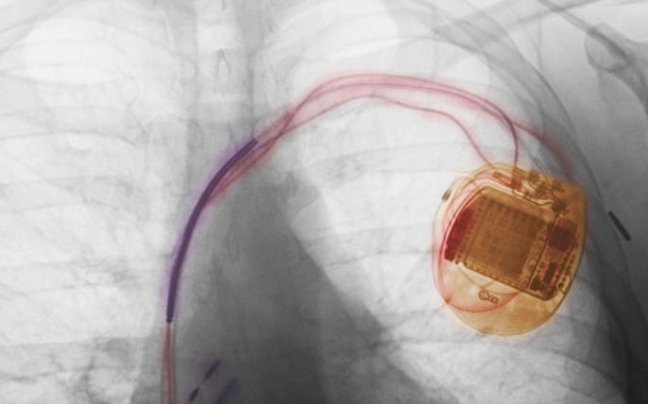

1958: Ο Σουηδός δρ. Εικ Σένινγκ εμφυτεύει στον ασθενή Άρνε Λάρσον τον πρώτο εσωτερικό βηματοδότη, ο οποίος είχε εφευρεθεί στις αρχές του ίδιου χρόνου από τον επίσης Σουηδό, Ρούνε Έλμκβιστ.